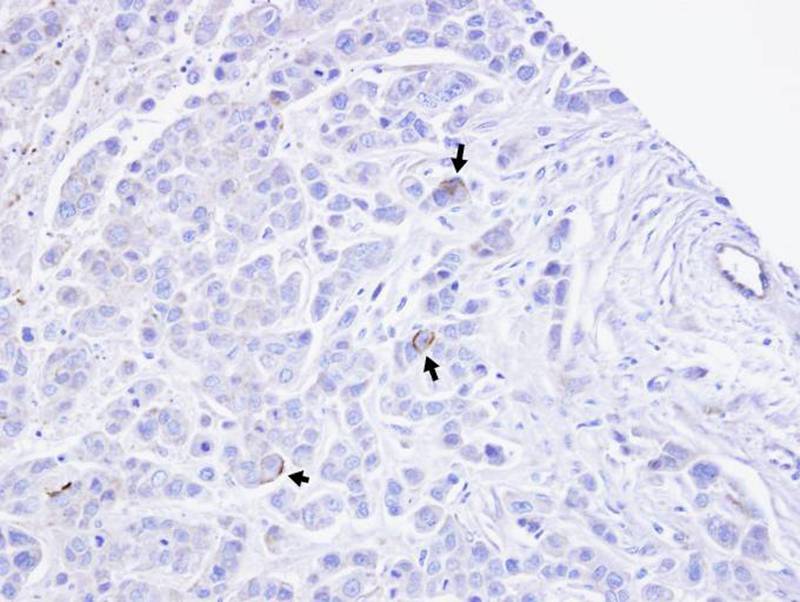

Immunohistochemical analysis of paraffin-embedded MDAMB468 xenograft, using TRPM2 antibody at 1: 100 dilution.